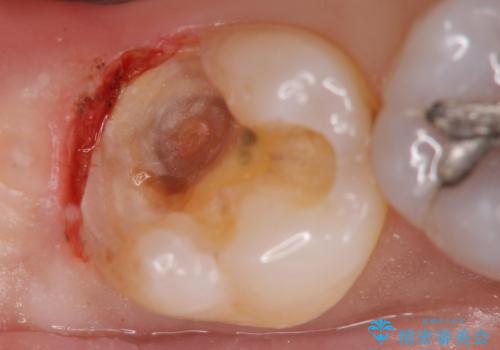

奥歯の深い場所に二次う蝕が確認されました。

歯肉を整理し、今後同じことを繰り返さないよう精度の良いゴールドアンレーで修復処置を行いました。